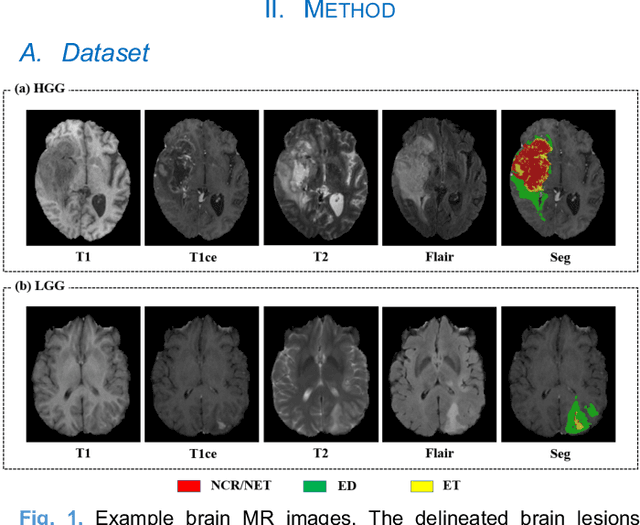

Abstract:Brain tumor segmentation based on multi-modal magnetic resonance imaging (MRI) plays a pivotal role in assisting brain cancer diagnosis, treatment, and postoperative evaluations. Despite the achieved inspiring performance by existing automatic segmentation methods, multi-modal MRI data are still unavailable in real-world clinical applications due to quite a few uncontrollable factors (e.g. different imaging protocols, data corruption, and patient condition limitations), which lead to a large performance drop during practical applications. In this work, we propose a Deeply supervIsed knowledGE tranSfer neTwork (DIGEST), which achieves accurate brain tumor segmentation under different modality-missing scenarios. Specifically, a knowledge transfer learning frame is constructed, enabling a student model to learn modality-shared semantic information from a teacher model pretrained with the complete multi-modal MRI data. To simulate all the possible modality-missing conditions under the given multi-modal data, we generate incomplete multi-modal MRI samples based on Bernoulli sampling. Finally, a deeply supervised knowledge transfer loss is designed to ensure the consistency of the teacher-student structure at different decoding stages, which helps the extraction of inherent and effective modality representations. Experiments on the BraTS 2020 dataset demonstrate that our method achieves promising results for the incomplete multi-modal MR image segmentation task.

Abstract:Radiomics and deep learning have shown high popularity in automatic glioma grading. Radiomics can extract hand-crafted features that quantitatively describe the expert knowledge of glioma grades, and deep learning is powerful in extracting a large number of high-throughput features that facilitate the final classification. However, the performance of existing methods can still be improved as their complementary strengths have not been sufficiently investigated and integrated. Furthermore, lesion maps are usually needed for the final prediction at the testing phase, which is very troublesome. In this paper, we propose an expert knowledge-guided geometric representation learning (ENROL) framework . Geometric manifolds of hand-crafted features and learned features are constructed to mine the implicit relationship between deep learning and radiomics, and therefore to dig mutual consent and essential representation for the glioma grades. With a specially designed manifold discrepancy measurement, the grading model can exploit the input image data and expert knowledge more effectively in the training phase and get rid of the requirement of lesion segmentation maps at the testing phase. The proposed framework is flexible regarding deep learning architectures to be utilized. Three different architectures have been evaluated and five models have been compared, which show that our framework can always generate promising results.